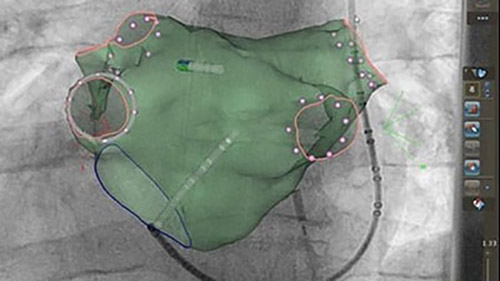

Live 3D echo and ICE integration improves orientation and soft tissue clarity, guides transeptal puncture and real-time tissue assessment, and supports complex procedures such as LAA closure.

Integrates all relevant images and information together in an interactive, intuitive and procedurally relevant way to expand clinical capabilities and enhance real time cross functional communication.